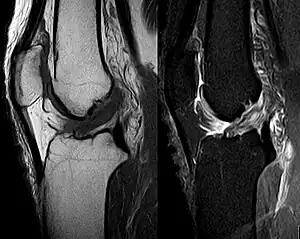

The unhappy triad, also known as a blown knee among other names, is an injury to the anterior cruciate ligament, medial collateral ligament, and meniscus. Analysis during the 1990s indicated that this 'classic' O'Donoghue triad is actually an unusual clinical entity among athletes with knee injuries. Some authors mistakenly believe that in this type of injury, "combined anterior cruciate and medial collateral ligament (ACL- MCL) disruptions that were incurred during athletic endeavors" always present with concomitant medial meniscus injury. However, the 1990 analysis showed that lateral meniscus tears are more common than medial meniscus tears in conjunction with sprains of the ACL.[1]

The unhappy triad occurs due to a lateral blow to the knee causing a rupture in the anterior cruciate ligament, medial collateral ligament, and meniscus. Injury is most often sustained when a lateral (from the outside) force impacts the knee while the foot is fixed on the ground. The strong valgus or rotary force to the knee tears the ACL, MCL, and medial meniscus all together. This type of injury occurs often in contact sports such as football, rugby, or motocross. During the injury, the leg is laterally rotated and over-abducted. In about 10% of cases, the force is applied to the opposite side of the knee, and the lateral and posterolateral ligaments are torn.

The classic O'Donoghue triad is characterized by an injury to three knee structures (in order):

- the anterior cruciate ligament

- the medial meniscus (however, lateral meniscus[1] injuries are more commonly seen among athletes, leading to the definition of the O'Donoghue triad most commonly used today.) [3][4][5]

- the medial collateral ligament (or "tibial collateral ligament")

The anterior cruciate ligament

The anterior cruciate ligament is one of the four crucial ligaments in the knee. It originates from the lateral condyle of the femur and goes to the intercondyloid eminence of the tibia. Its function is to provide stability in the knee and minimize stress across the knee joint. It also restrains excessive forward movement in the leg and limits rotational movements in the knee.

Injury

An anterior cruciate ligament injury results from excess tension on the ligament. This can come from a sudden stop or twisting motion of the knee. A few initial symptoms include swelling, knee instability, and pain. A popping sound or sensation may or may not be heard when the ACL first tears. A following symptom usually includes the feeling of the knee "giving out". Tearing of the ACL is the most significant injury because it leaves the knee unstable, which also causes the knee to lose its normal function.

Meniscus

The medial meniscus is a C-wedge shaped piece of cartilage that acts as a"shock absorber" between the femur and the tibia. Each knee has two menisci, one at the outer edge and one at the inner edge of the knee. The menisci are tough and rubber-like to help cushion the joint and help keep it stable.

The lateral meniscus is also known as the external semilunar fibrocartilage. It is a fibrocartilage band on the lateral side of the knee joint and can easily be injured with torsional stress or direct force.

Each knee has a medial and lateral meniscus, consisting of connective tissue and collagen fibers. Menisci are needed to distribute the body weight across the knee. Without them, the body weight is distributed unevenly on the femur and tibia, possibly leading to early arthritis in the knee joint. The menisci are nourished by small blood vessels, but each has a large central section which is avascular and does not get a direct blood supply. This poses a problem in a meniscus injury, as blood flow is diminished and the avascular areas tend to not heal.

The tear of meniscus is among the most common knee injuries. It is usually caused by torsional stress; twisting or turning of the knee too quickly with the foot planted on the ground while the knee is flexed. The feeling of a "pop" in the knee is usually felt when the meniscus is torn. Athletes, particularly those who participate in contact sports, are at a greater risk for meniscal tears. Sports-related meniscal tears often occur with other knee injuries, such as an anterior cruciate ligament tear.

Medial collateral ligament

Because the medial collateral ligament resists widening of the inside of the knee joint, the ligament is usually injured when the outside of the knee joint is struck. This force causes the outside of the knee to buckle, and the inside to widen. When the MCL is stretched too far, it is susceptible to tearing and injury. This is the injury seen by the action of "clipping" in a football game.

An injury to the MCL may occur as an isolated injury, or it may be part of a complex injury to the knee. Other ligaments ACL, or meniscus, may be torn along with a MCL injury.